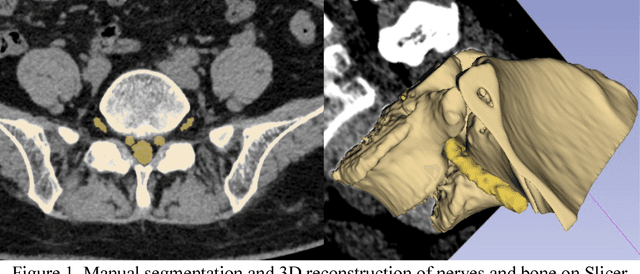

Abstract:Background and objective: Combined evaluation of lumbosacral structures (e.g. nerves, bone) on multimodal radiographic images is routinely conducted prior to spinal surgery and interventional procedures. Generally, magnetic resonance imaging is conducted to differentiate nerves, while computed tomography (CT) is used to observe bony structures. The aim of this study is to investigate the feasibility of automatically segmenting lumbosacral structures (e.g. nerves & bone) on non-contrast CT with deep learning. Methods: a total of 50 cases with spinal CT were manually labeled for lumbosacral nerves and bone with Slicer 4.8. The ratio of training: validation: testing is 32:8:10. A 3D-Unet is adopted to build the model SPINECT for automatically segmenting lumbosacral structures. Pixel accuracy, IoU, and Dice score are used to assess the segmentation performance of lumbosacral structures. Results: the testing results reveals successful segmentation of lumbosacral bone and nerve on CT. The average pixel accuracy is 0.940 for bone and 0.918 for nerve. The average IoU is 0.897 for bone and 0.827 for nerve. The dice score is 0.945 for bone and 0.905 for nerve. Conclusions: this pilot study indicated that automatic segmenting lumbosacral structures (nerves and bone) on non-contrast CT is feasible and may have utility for planning and navigating spinal interventions and surgery.